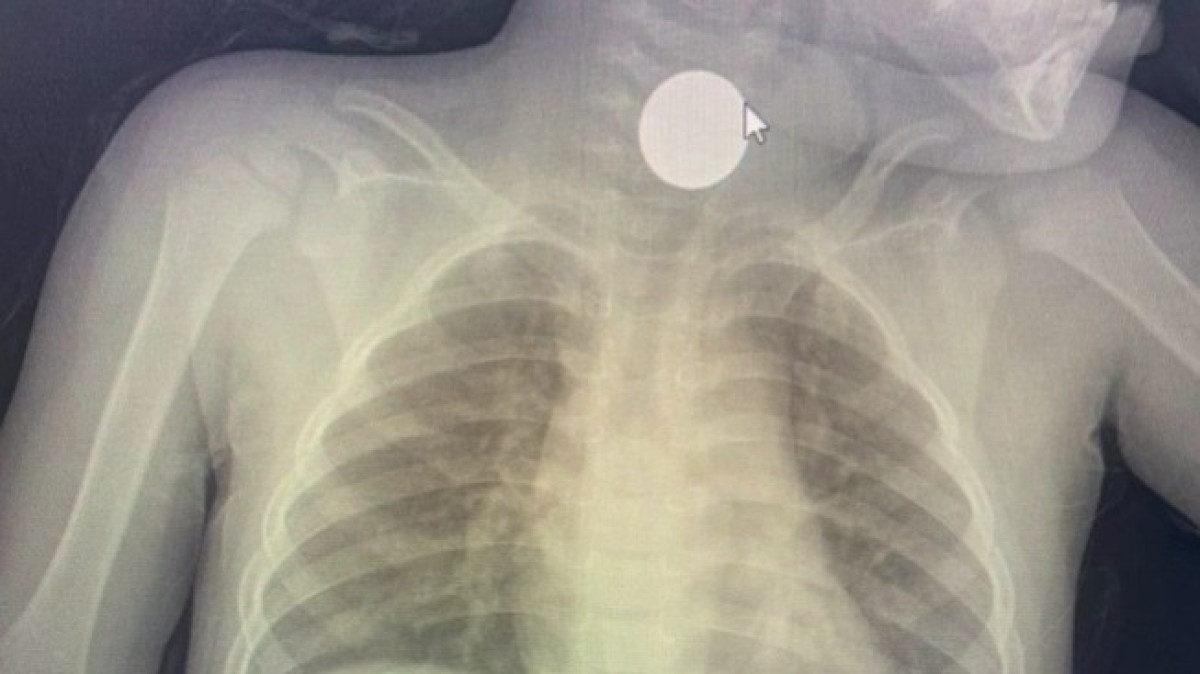

Жамбыл облысында дәрігер 3 жасар баланың өңешінен 100 теңгені алып шықты

Жамбыл облысы Байзақ аудандық орталық ауруханасының дәрігері өңешіне тиын тұрып қалған баланы аман алып қалды. 3 жасар бала абайсызда 100 теңгелік тиынды жұтып қойған.

Дәрігер 3 жасар баланың өңешінен 100 теңгені алып шыққан сәттегі видеоны жариялады.

3 жасар бала 100 теңге жұтып қойған. Абырой болғанда тыныс жолдарына өтпеген. Балаларыңызға абай болыңыздар! - деді дәрігер Сейітқалық Еділ.